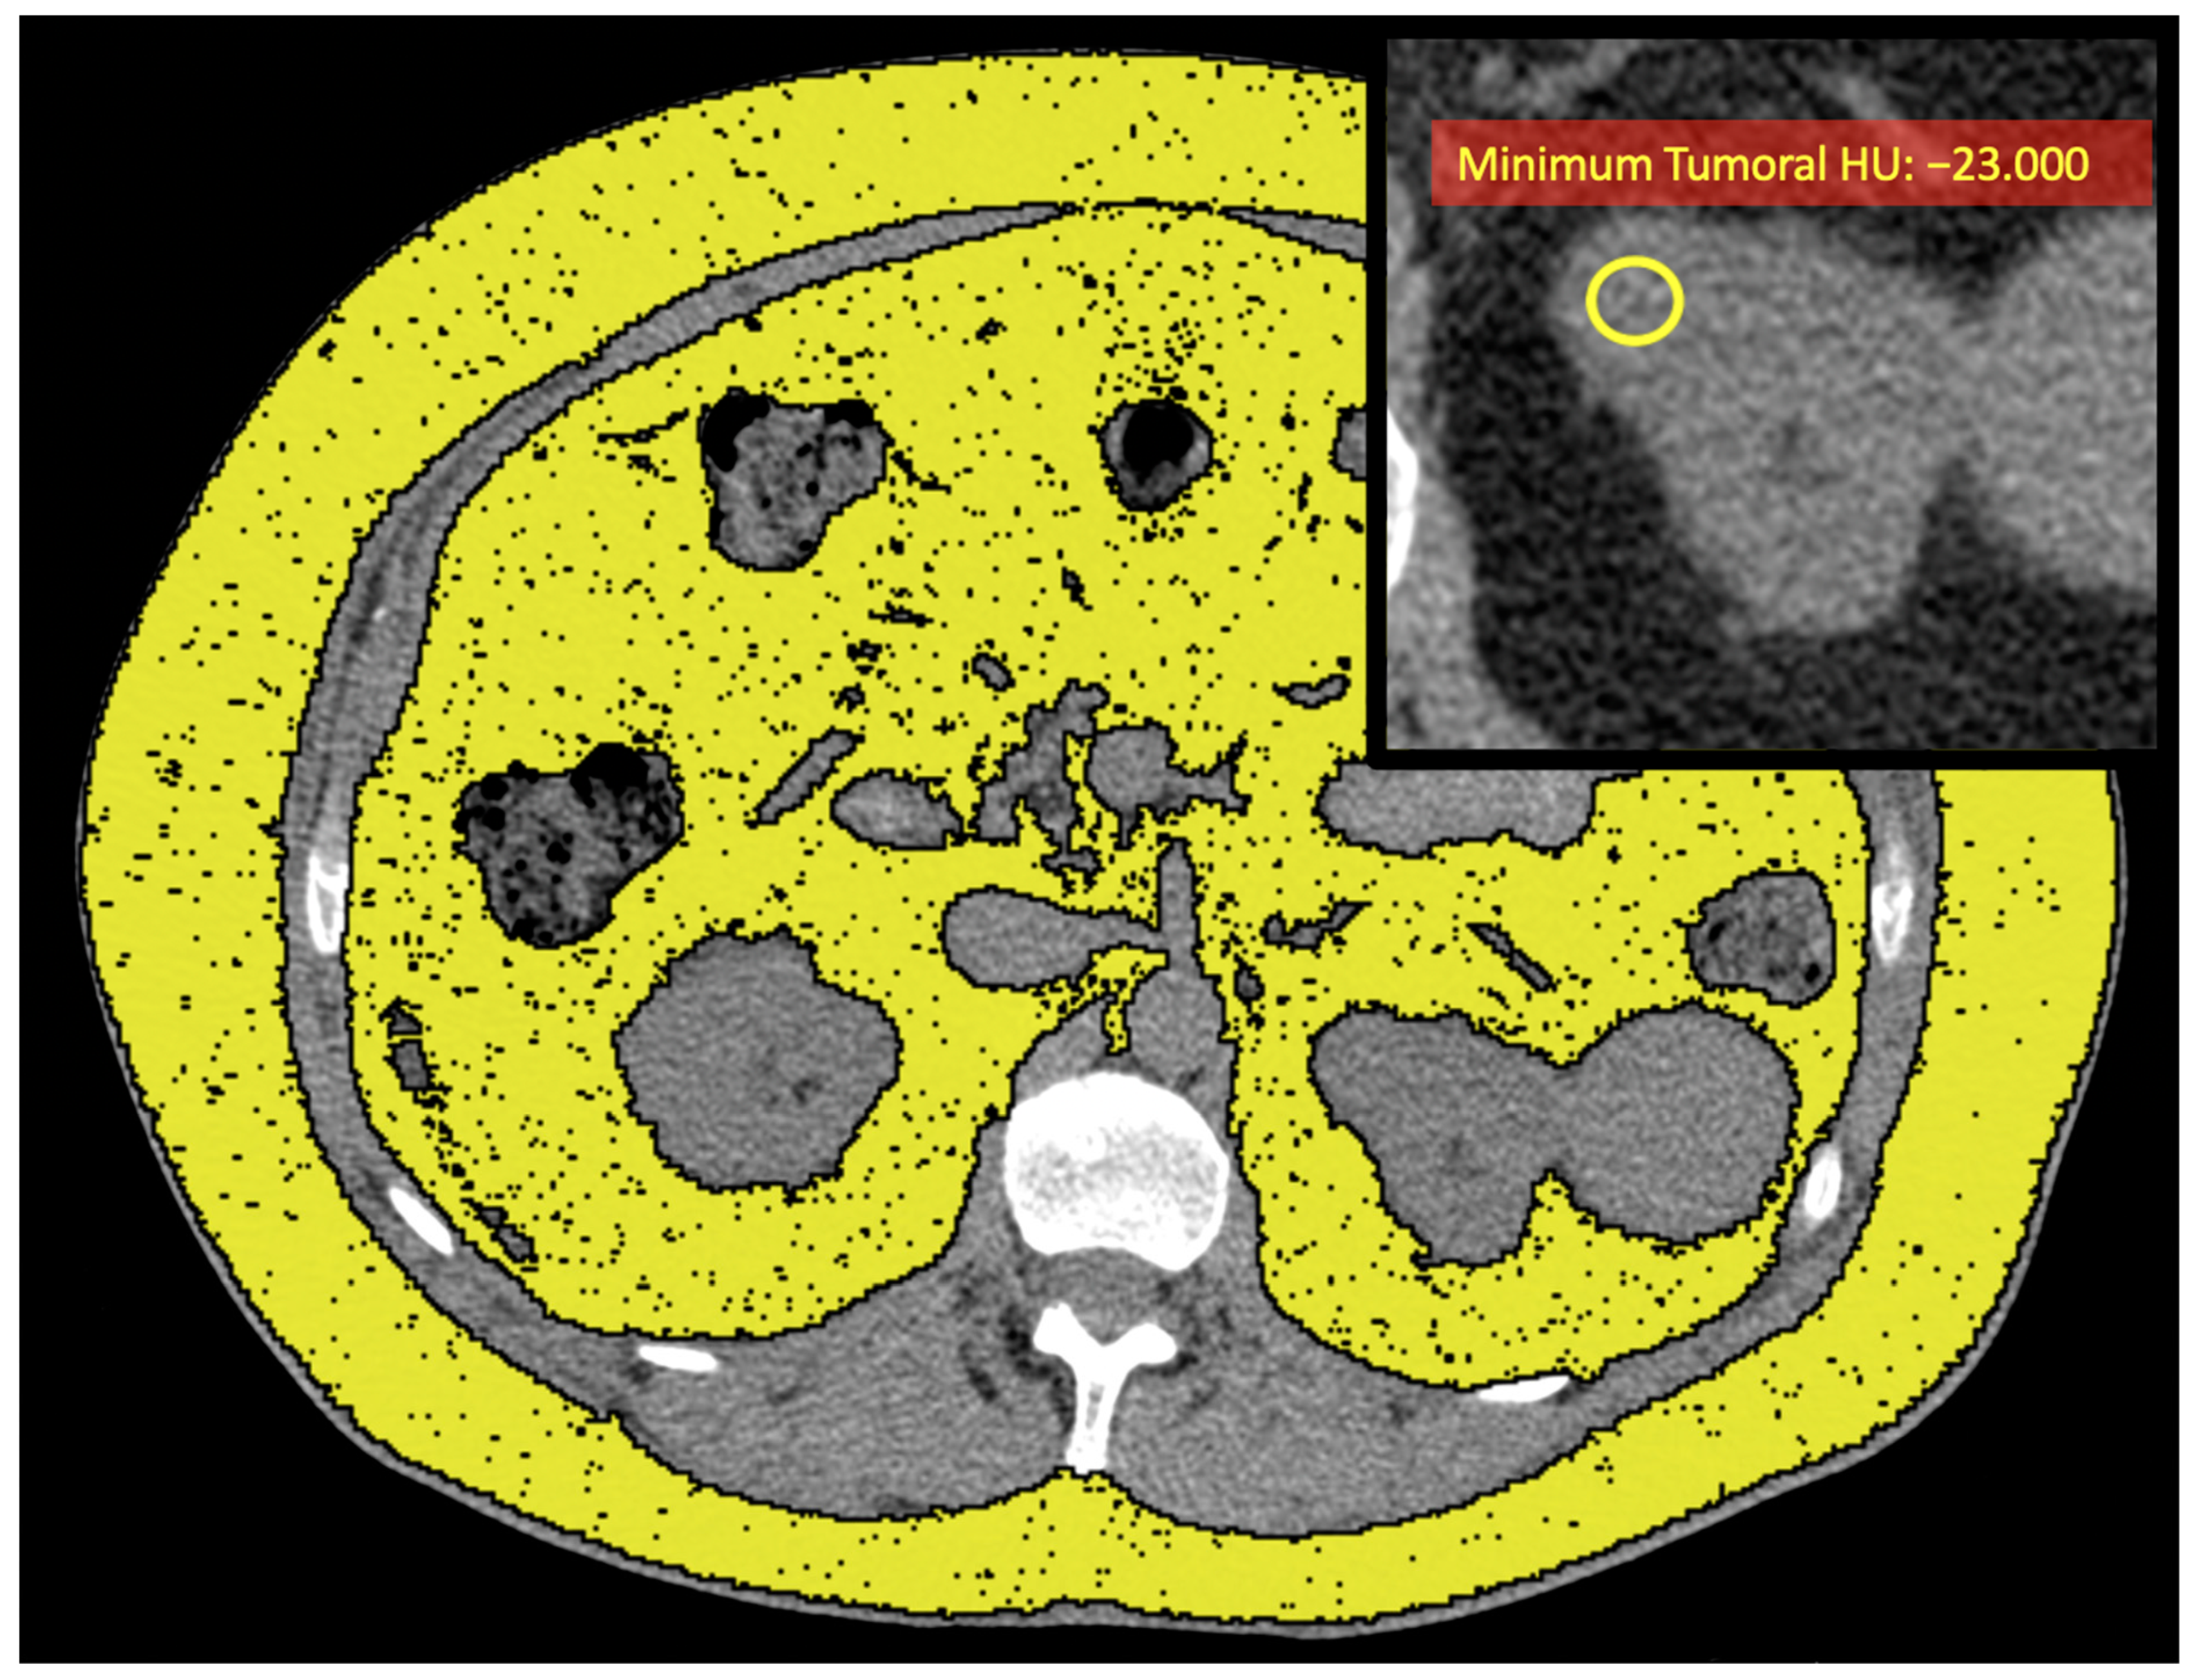

| Tumoral HUs Median Minimum Maximum | 35 (30, 40) −5 (−18, 3) 77 (67, 91) |

| Tumoral HUs | |||

| Median | 32 (27, 37) | 30 (24, 32) | 0.10 |

| Minimum | −6 (−16, 3) | −23 (−38, −13) | 0.006 |

| Maximum | 74 (62, 87) | 71 (63, 100) | 0.5 |